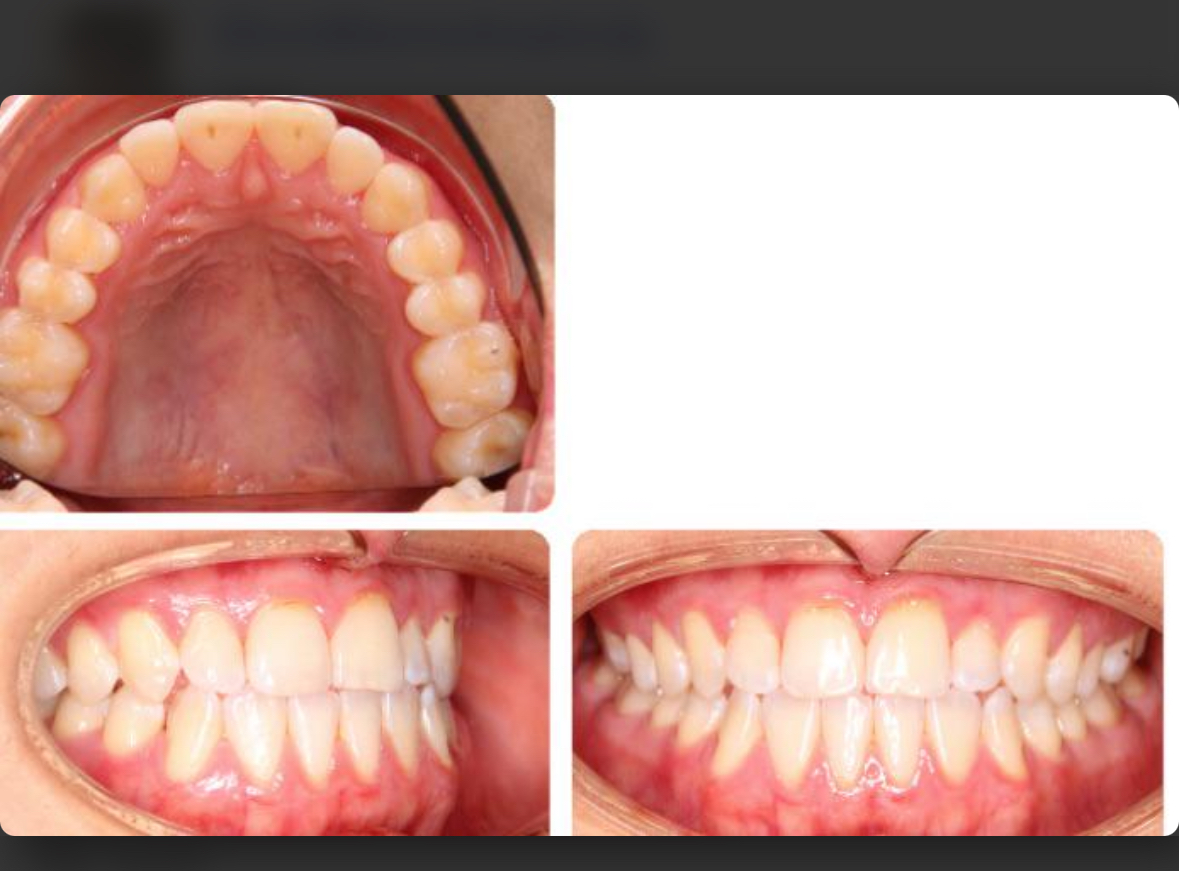

This is the guys teeth this can be decomposition without extractions he’s just rushing and going to a shit ortho

This is kinda doxxing and decomp doesnt work that way, he is class 3 and his teeth doesnt sit right on his bone if you look at the scans they are tilted from the nasal base and then to the lower jaw. But obv its not possible to tilt them so he actually can move maxilla without peoclined teeth so he will look like a ape post op. Thats also the reason why looking at this pics from below when the bone above is too short either way

Its like this(pic below), wow the front teeth is infront but obv the teeth is proclined so he looks like a ape. This dude also needs extractions, because there will be no room for to reverse the proclined teeth otherwise. And having this proclined teeth is not good for longevity either way